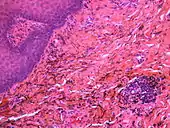

If necessary, the diagnosis can be confirmed histologically by excisional biopsy, which excludes nevi and melanomas.[3]: 138 If a biopsy is taken, the histopathologic appearance is:[1]

- Pigmented fragments of metal within connective tissue

- Staining of reticulin fibers with silver salts

- A scattered arrangement of large, dark, solid fragments or a fine, black or dark brown granules

- Large particles may be surrounded by chronically inflamed fibrous tissue

- Smaller particles surrounded by more significant inflammation, which may be granulomatous or a mixture of lymphocytes and plasma cells